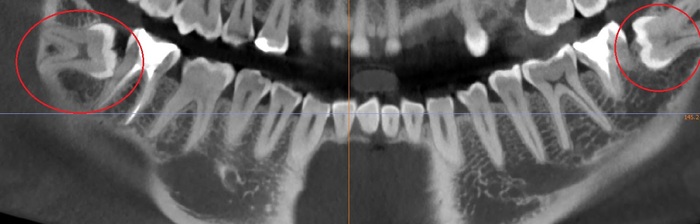

Сага о стоматологии. Глава 37. Можно ли удалить сразу все зубы мудрости за один раз?

Для ЛЛ: можно, но не всем и не всегда.

Ясное дело, что разом все восьмерки, которые полностью лежат в кости, я не взялся бы удалять в амбулаторных условиях сразу даже себе, так как риск осложнений крайне высок, а пациент потом на утро проклянет весь твой род до пятого колена, так как потом будет ПИСЕЦ КАК ПЛОХО. Как вот тут.

Теперь рассмотрим один из примеров. Вчера это был крепкий 18-летний парень, сын медсестры, он абсолютно здоров и готовится к службе в армии, куда уезжает через недели 3. Но вот беда, начали резаться зубы мудрости, а пользоваться потом услугами военной карательной стоматологией где-то у черта на рогах желания нет. Он стойко переносит все тяготы службы и лишения военной службы любого лечения, да и в случае чего мама ужалит дома необходимым препаратом.

Его восьмерки лежали под десной, но кость пилить не приходилось, поэтому удаление всех четырех зубов прошло за минут 30

Положили тромбоцитарную массу, ушили, дали рекомендации, отпустили.